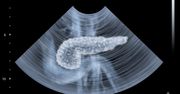

Trzustka - budowa, położenie, funkcje, najczęstsze choroby, dieta

Zapalenie trzustki - przyczyny, rozpoznanie, leczenie